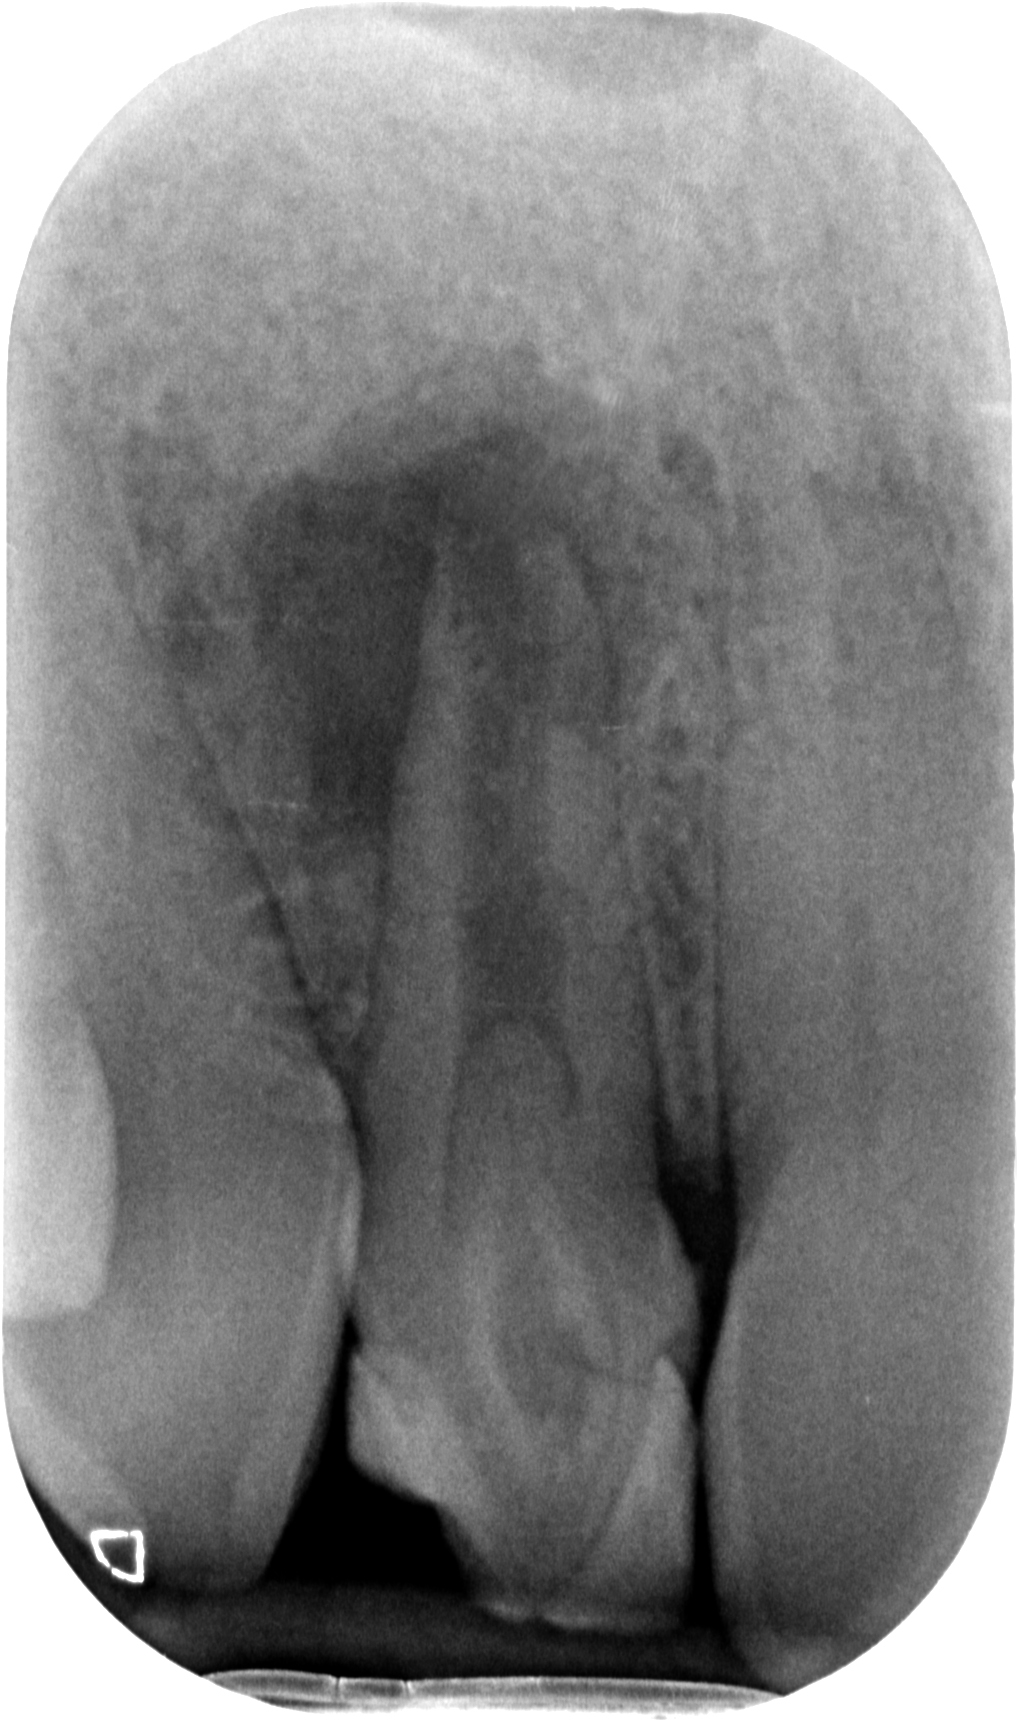

Il primo era questo

La proprietaria del dente, una ragazzina di 16 anni, da tempo lamentava gonfiore e dolore che scompariva solo con terapie antibiotiche. Il dentista precedente aveva semplicemente corretto la forma del dente con un composito orrendo. La diagnosi non aveva saputo farla. Aveva solo saputo dire che era un dente che si poteva solo estrarre.

Con l’ausilio della Cone Beam sono riuscito a identificare che il dente aveva due canali e una radice molto palatoversa: per accedere a questi canali, separati tra loro dall’istmo di smalto invaginato, potevo fare una cavità perpendicolare al dente a livello vestibolare e una palatina.